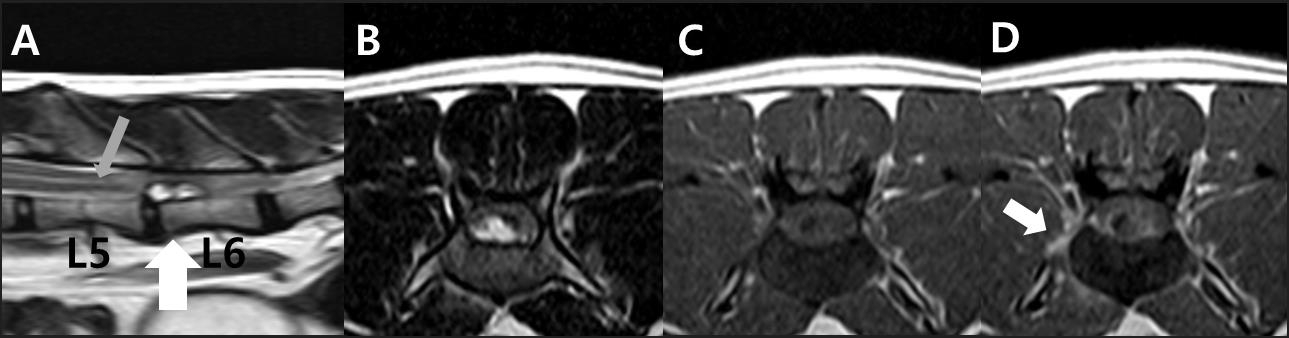

고양이 척수 경막외 섬유성 수막종의 MRI 영상

연구진은 해당 증례가 MRI 검사에서 추간판 탈출증과 유사한 소견을 보여 감별 진단이 어려웠다는 점을 지목했다. 환자는 후궁 절제술과 조직검사를 통해 섬유성 수막종으로 최종 확진됐다.

이러한 경막외 수막종은 매우 드문 형태로, 비전형적 척추 병변의 진단에 중요한 참고 사례가 될 것으로 평가된다.